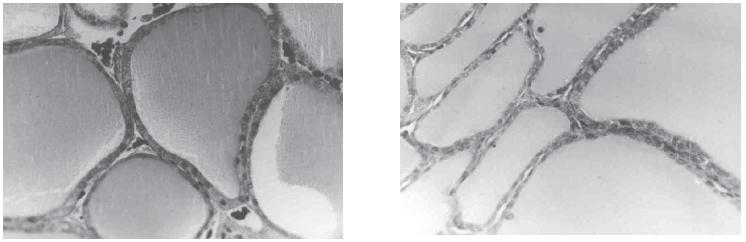

De la misma manera, en los individuos sacrificados se pudo observar aumento del tamaño de la glándula tiroides, el cual guarda relación con la dosis de nitrato administrada, pues los individuos del grupo que consumió la mayor dosis de nitrato presentaron el mayor tamaño glandular. El análisis histológico de las muestras procedentes de estos animales demostró la aparición de cambios relacionados con la dosis de nitrato consumida. En la glándula tiroides de los animales del grupo 3, se observó una disminución del coloide con un cambio estructural de las células foliculares, que pasaron de cúbicas a planas (figura 3). En órganos como pulmón, riñón e hígado, de los animales aparentemente sanos, no se observaron cambios patológicos.

FIGURA 3. Glándula tiroides de pollos aparentemente sanos. La fotografía de la derecha muestra un corte histológico de glándula tiroides de un pollo aparentemente sano del grupo 3. Nótese el aplanamiento del epitelio glandular en las muestras de tiroides de los individuos que sobrevivieron a todo el ciclo del grupo 3 (derecha) al compararlo con la muestra obtenida de la glándula tiroides de los animales sobrevivientes del grupo 0. Tricrómica de Masson. 435 X.

El estudio microscópico de los cortes de la glándula tiroides obtenidos de animales aparentemente sanos mostró cambios graduales sugestivos de bocio hipofuncionante en los individuos de los grupos 2 y 3 (figura 3), caracterizados por un aumento del diámetro promedio de los folículos, una disminución de la apetencia tintorial del coloide y un aplanamiento del epitelio folicular, el cual en algunas zonas llega a tener una altura de tan solo 3 µm. Esto contrasta con la histología de las tiroides de los individuos de los grupos 0 y 1 donde la altura de las células epiteliales foliculares se encuentra entre 7,5 y 13 µm.El efecto bociogénico de los nitratos ha sido sugerido y comprobado ya por varios autores (13), hecho que probablemente puede explicar las diferencias macroscópicas y microscópicas de la glándula tiroides en los animales sacrificados. Al estar presente un agente bociogénico en la dieta, los niveles sanguíneos de hormonas tiroideas van a disminuir, lo que va a ser compensado con un aumento en la liberación de TsH, con una respuesta glandular que puede ser efectiva o no. Así, este estímulo induce un aumento del tamaño glandular causado por hipertrofia celular el cual tiene como fin aumentar los niveles circulantes de hormonas tiroideas; el aumento del tamaño glandular será entonces proporcional al efecto del agente bociogénico, tal como ocurrió en el grupo número 3, donde el tamaño tiroideo fue el mayor de todos los observados, pues como se recuerda este grupo recibió la dosis más alta de nitrato. No obstante, a pesar de este estado de hipofunción tiroidea, y de lo sugerido en anteriores estudios en los que se informó una disminución del peso en animales que recibieron una adición de nitrato, en el presente trabajo no se notó ninguna diferencia apreciable en cuanto al peso se refiere entre aquellos animales del grupo 0 y los que recibieron adición de nitrato (datos no mostrados).